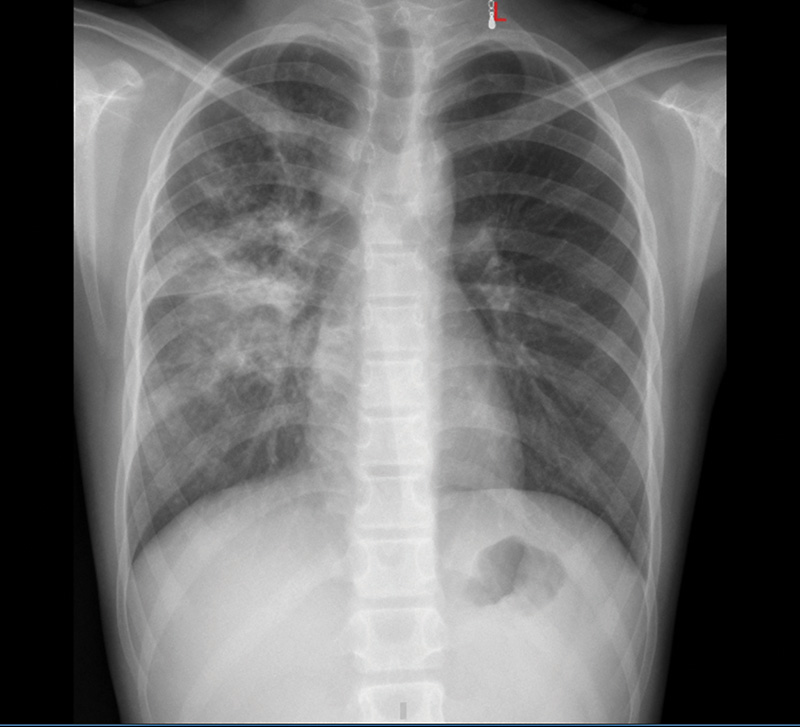

At the Emergency Department of the Central Tropical Hospital, the patient was treated with a combination of antibiotics, antifungals and continuous blood filtration. However, after only a few days, he developed subcutaneous emphysema in the neck and chest area. X-ray and CT scan results revealed pleural and mediastinal emphysema, causing acute cardiac tamponade.

The patient was placed on ECMO (extracorporeal membrane oxygenation) for support. The patient was then transferred to the Intensive Care Unit in a state of septic shock, multiple organ failure (including liver failure, kidney failure and respiratory failure), and continuous blood filtration and vasopressor maintenance. Bronchoscopy revealed a lot of pus and pseudomembranes covering the bronchial mucosa, a serious consequence of Whitmore bacteria causing lung damage.